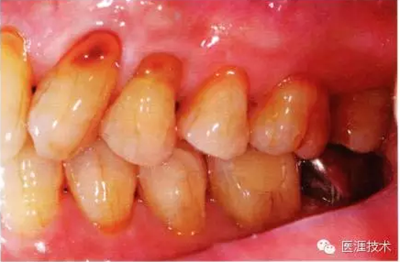

患有牙周病的牙周組織的臨床照片

上海品瑞邁格磁致伸縮治療儀

56歲牙周炎男性的臨床照片

正在服用高血壓藥中的56歲男性。菌斑控制得不好。通過牙周探診,全頜有4~6mm的牙周袋,在X光片中可以看到全頜中度牙槽骨吸收,磨牙處一個地方是重度牙槽骨吸收。通過比較牙周病進展狀態(tài),邊緣部有大范圍浮腫(發(fā)紅、腫脹),和纖維性肥厚。這也可能是服用中的降壓藥的副作用導致的。因為牙齦、牙槽骨比較厚,牙齦呈架子狀。